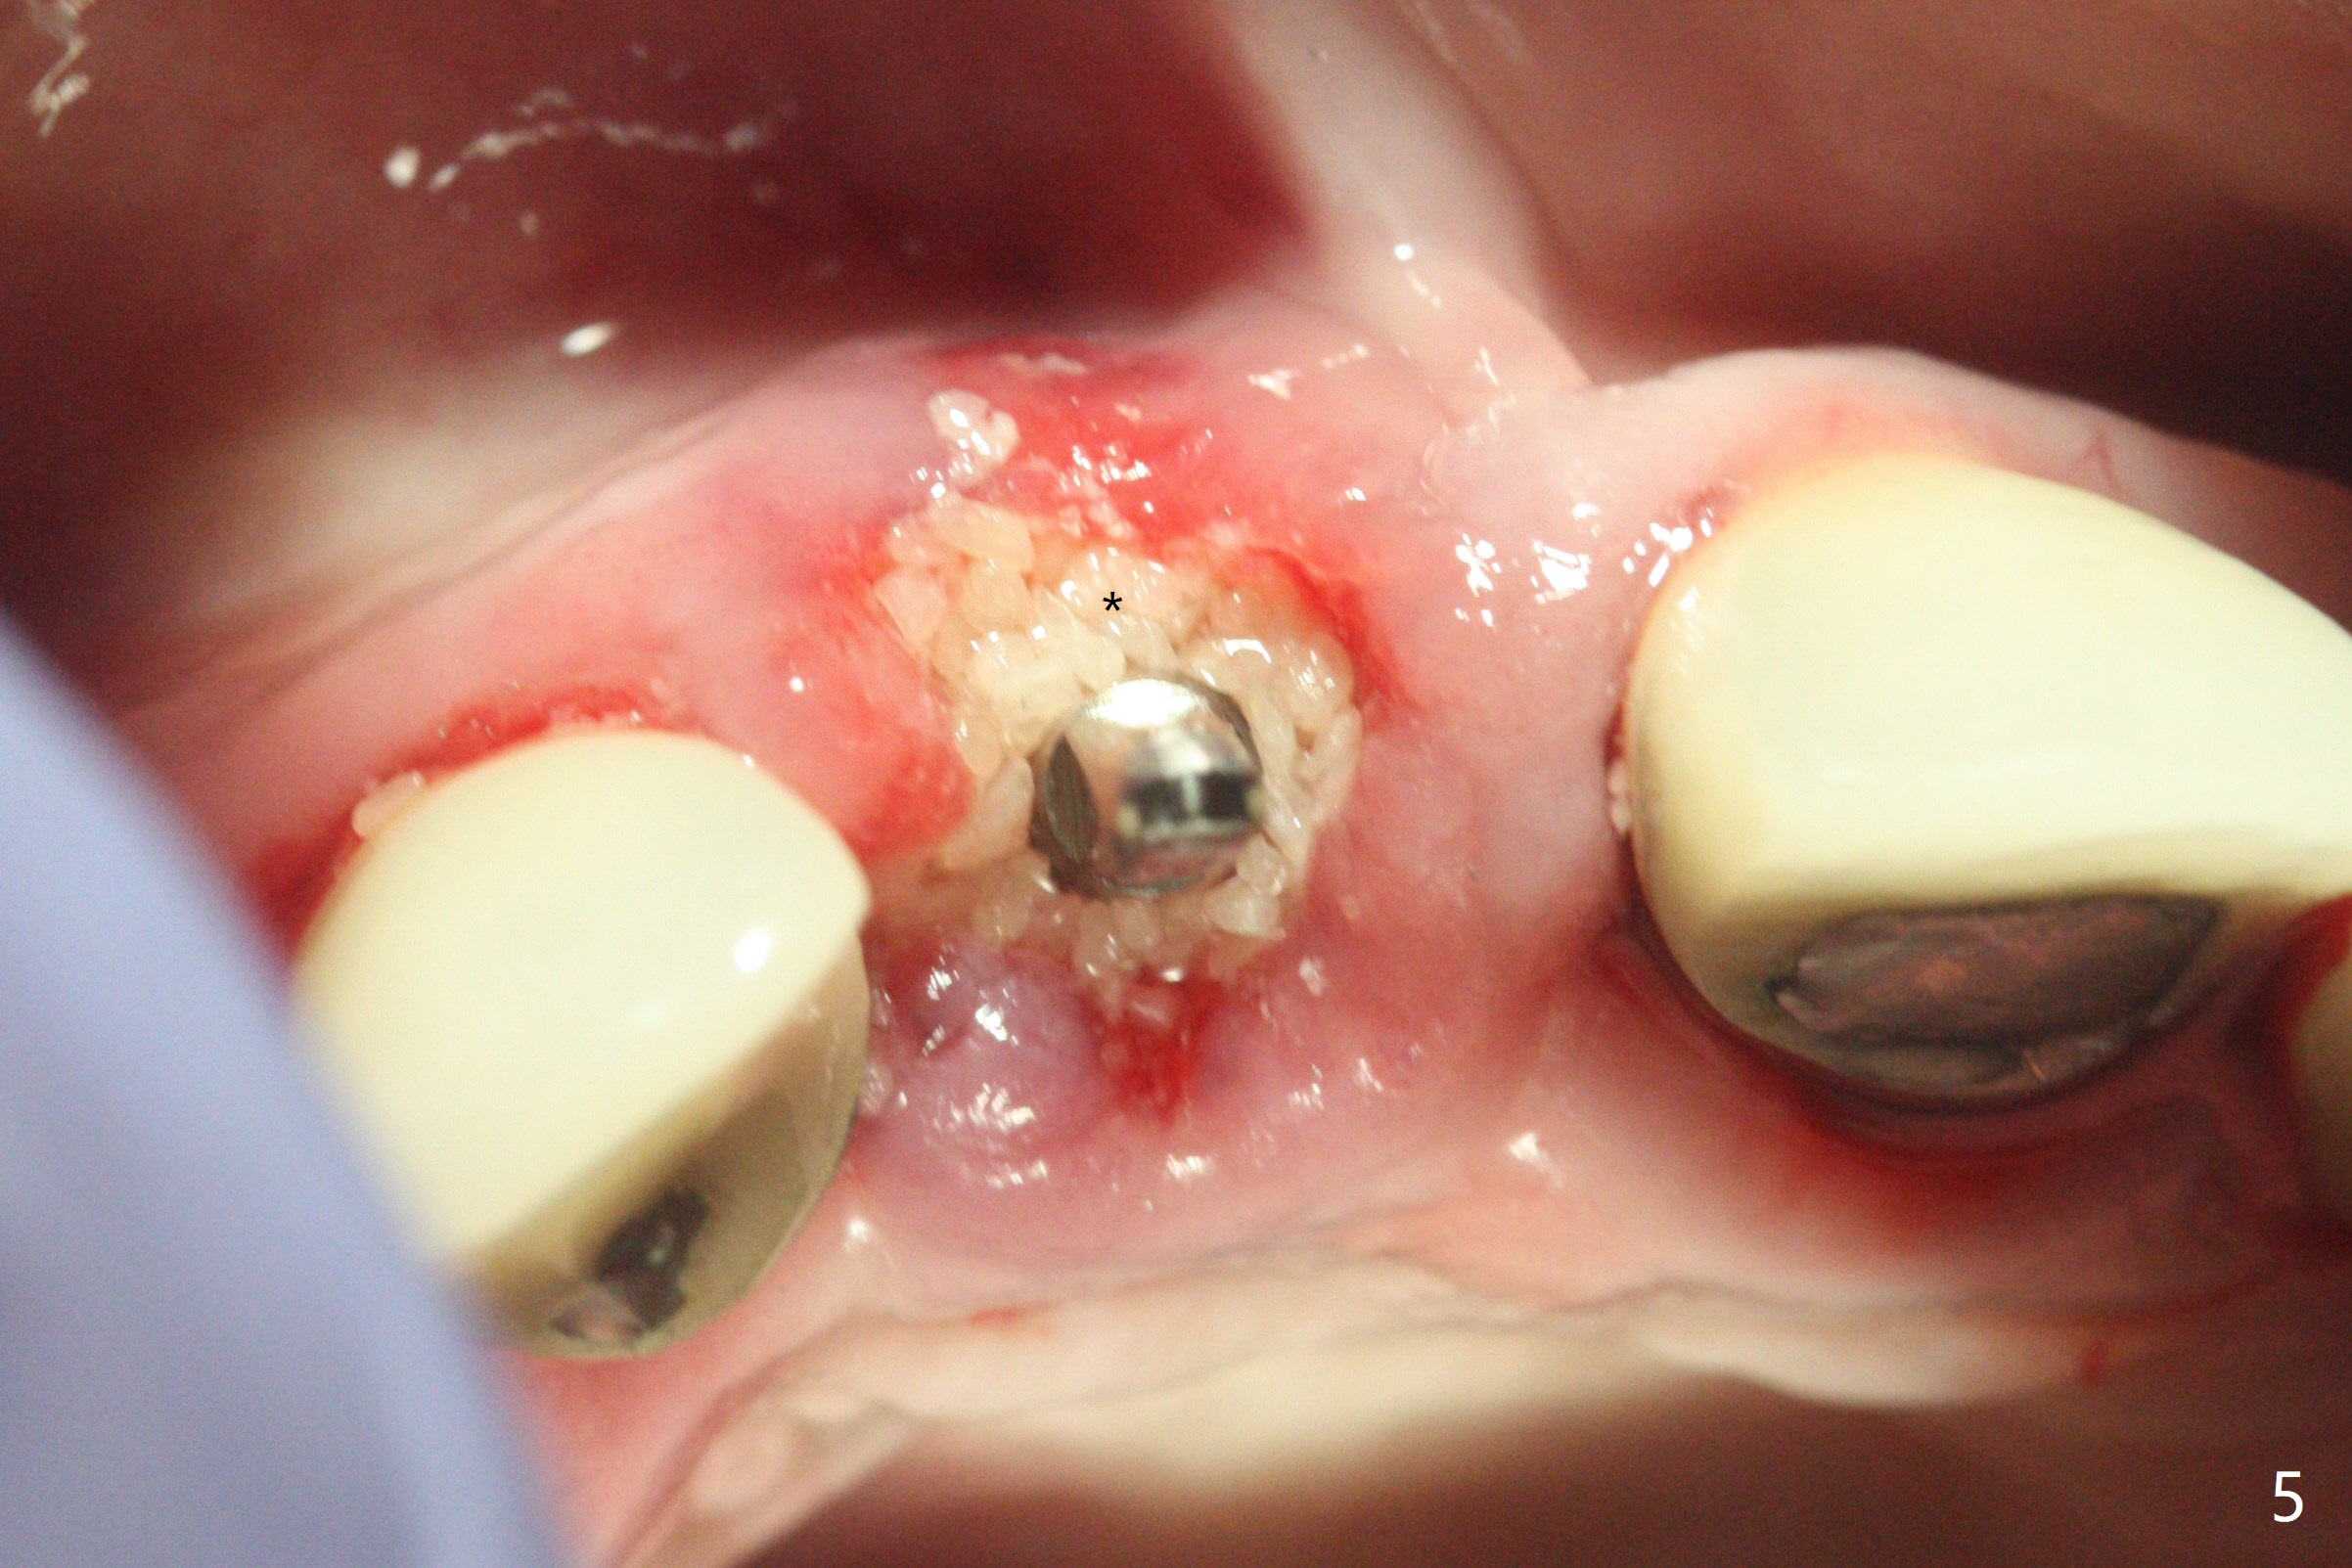

徒手初步钻洞显示方位不对(图一),重新钻洞方位尚可,好像接近鼻底(图二:红线);植入3x11.5毫米一段式植体(图三),3-5个螺纹暴露,植体似乎接近鼻底;旋转植体三趟,植体仿佛卡人鼻底,扭力大约35Ncm,植入粘性骨粉(图四,五:*)前,塞入PRF膜,紧贴颊侧粘膜,促进瘘道愈合。骨粉不仅围绕植体,而且紧贴邻牙牙根(图六(第二轮植骨:overgrafting):<)。病人术后第二周开始使用水牙线,术后三周牙龈健康多了,瘘道消失(图七)。术后六周颊侧骨壁开始塌陷(图八:>),临时牙冠颊侧颈部显得隆起(*)。调整后,牙冠外形改善(图十一至十三),取模前颊侧牙龈缘有可能下降,两个中切牙龈缘可能一致。术后3.5个月骨粉形态(图十四)与术后即刻(图六)有所不同。颊侧牙龈仍红肿轻度触痛(图十五),可能因为临时牙冠不利于局部卫生,所以决定取模制作永久性牙冠。粘固时使用临时胶水,并且涂抗菌素。另外一个可能因素是颊侧骨板薄(图十六:*),细菌感染植体螺纹,永久性牙冠粘固前,拍摄CT(放置cotton roll),必要时,植骨。永久性牙冠远中有缝隙,为了预防病人后悔,使用临时性粘固剂固定(图十七)。Return to No Caries DIO 下一个病例 一段式植体边缘制备 导板与内提升 Xin Wei, DDS, PhD, MS 1st edition 12/22/2020, last revision 06/15/2021